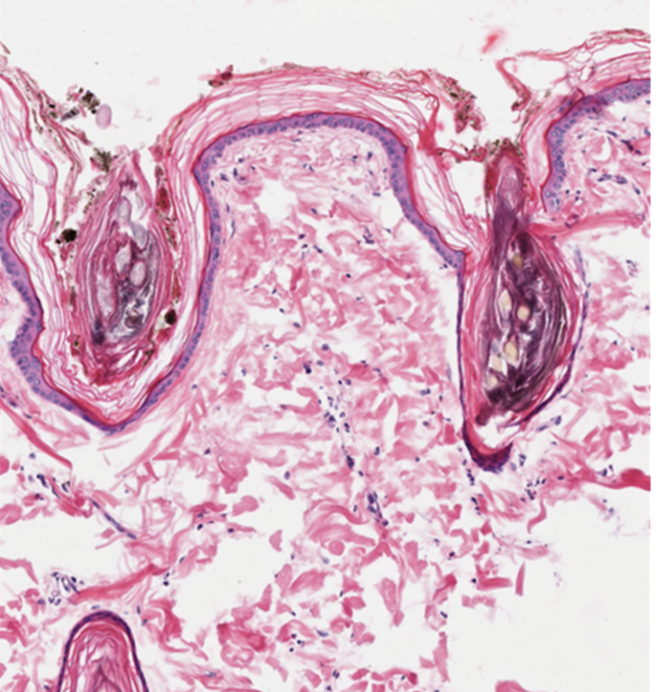

What are the gross features of this follicular hamartoma?

Follicular hamartomas present as plaques or nodules that have thick, brush like hairs protruding from the both the epidermal surface and into the dermis. The epidermis and dermis are usually thickened.

13

What is the prognosis for this dog? Will surgical excision of the mass be curative?

The prognosis is good for this patient. Follicular hamartomas are benign lesions and surgical removal is considered curative.